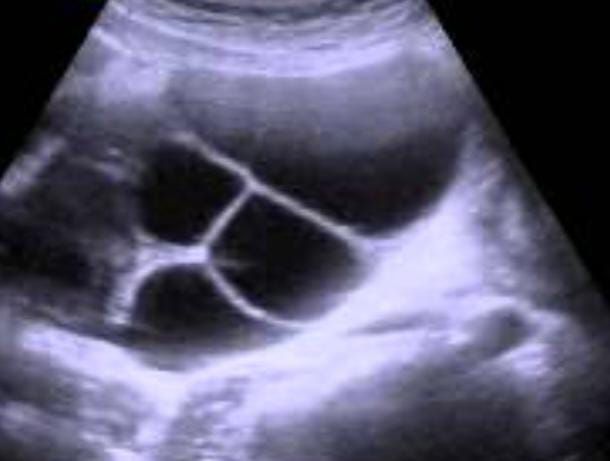

У меня так было в том году, после плохого роста ХГЧ на УЗИ увидели деформированное ПЯ и пузырёк рядом, решили подождать мож раздвоился, оказалось нет , через неделю их было 5 и Ре предположила пузырный занос и сказала срочно вакуум 🥺 ( фото прилагаю)в итоге не подтвердили пузырный, генетически не правильно развивался к сожалению. Надеюсь у Вас не так🙏 Изображение